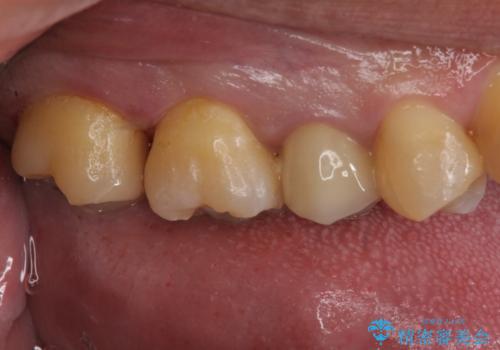

放置していた虫歯 セラミックインレーによる治療

虫歯の大きさ次第でクラウンかインレーのどちらかになるだろうとご説明させていただき、今回はセラミックインレーでの治療となりました。

治療後は食事の際の痛みもなくなり、快適に過ごせているそうです。